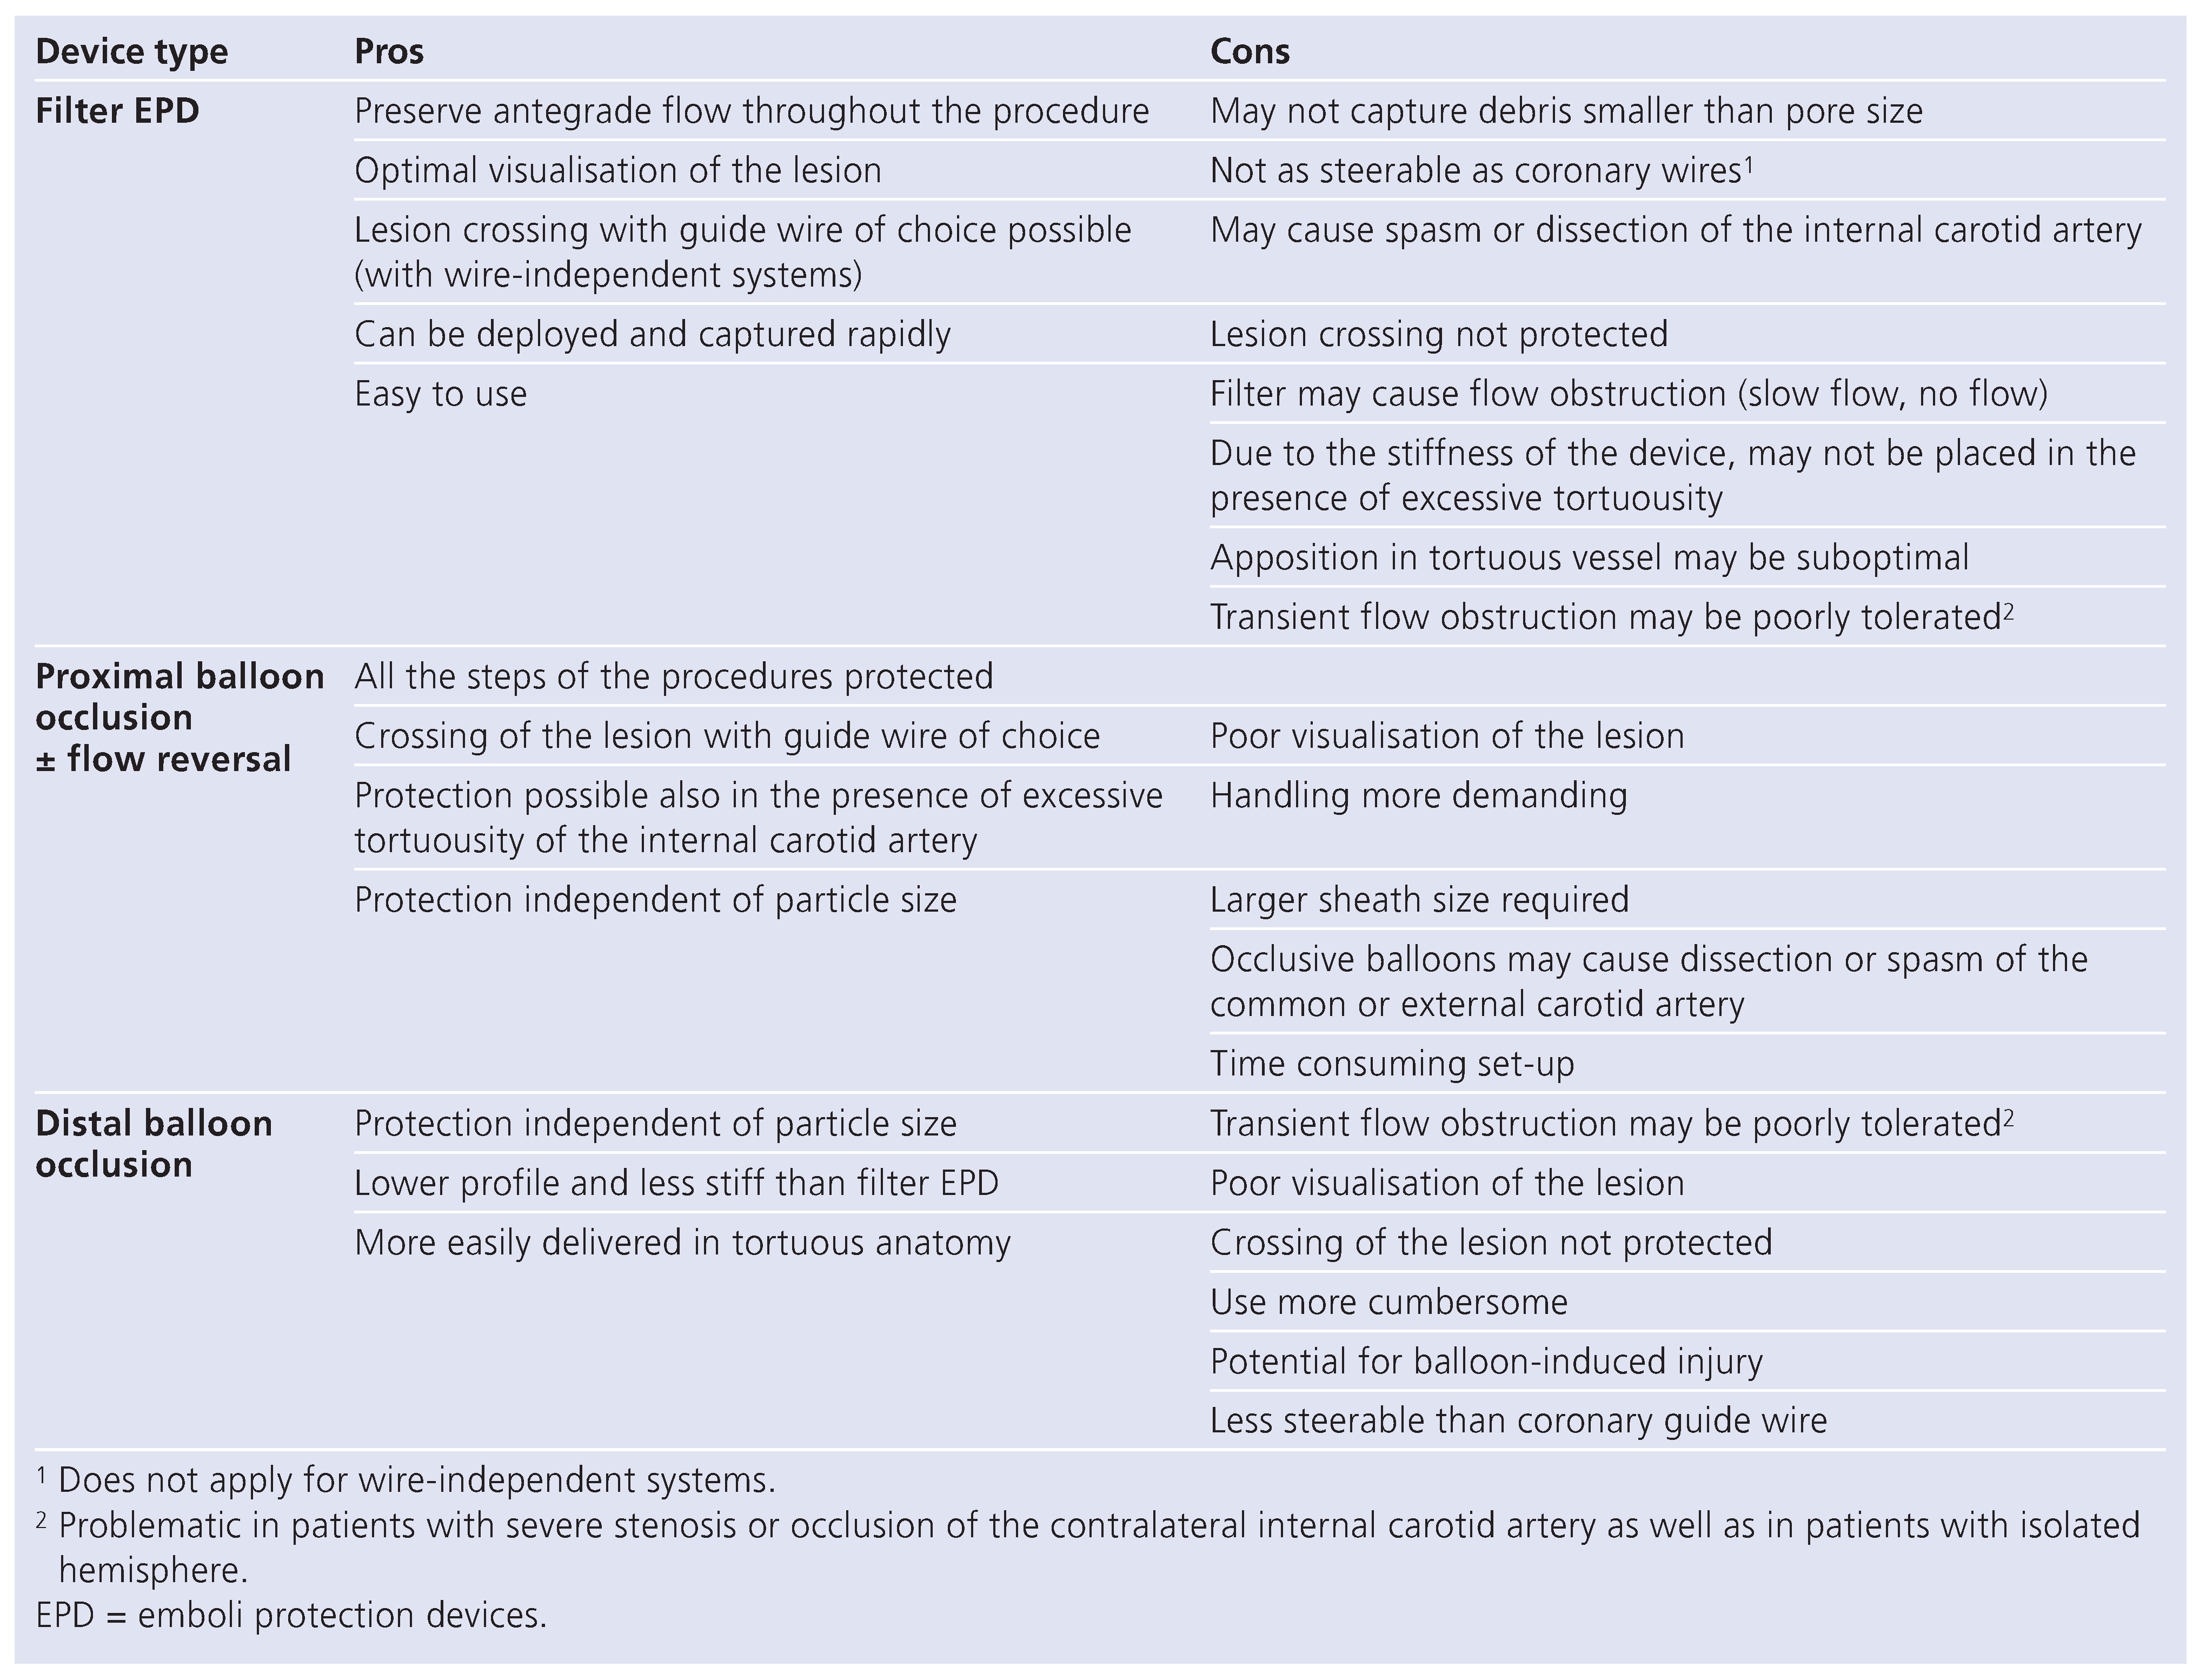

Carotid artery stenting